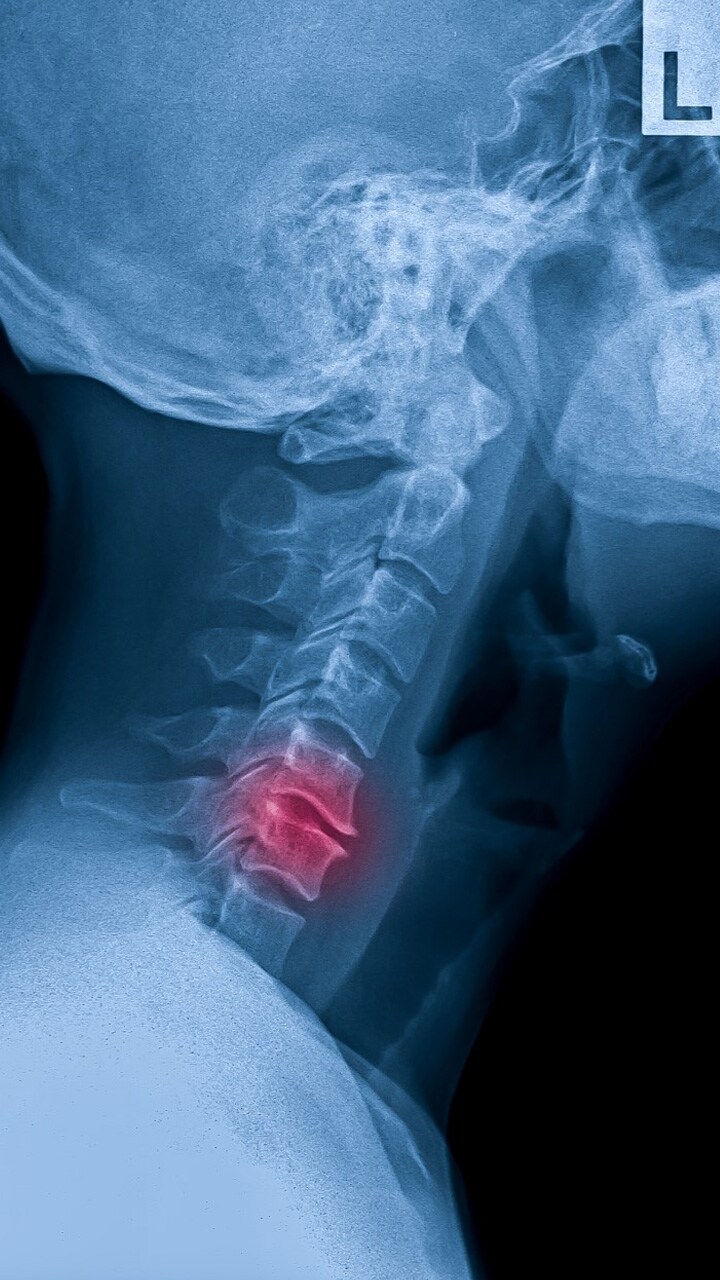

bone cancer symptoms

दर्द और सूजन

लगातार दर्द और सूजन चिंताजनक हो सकती है. दर्द आपको रात में नींद से जगा सकता है.